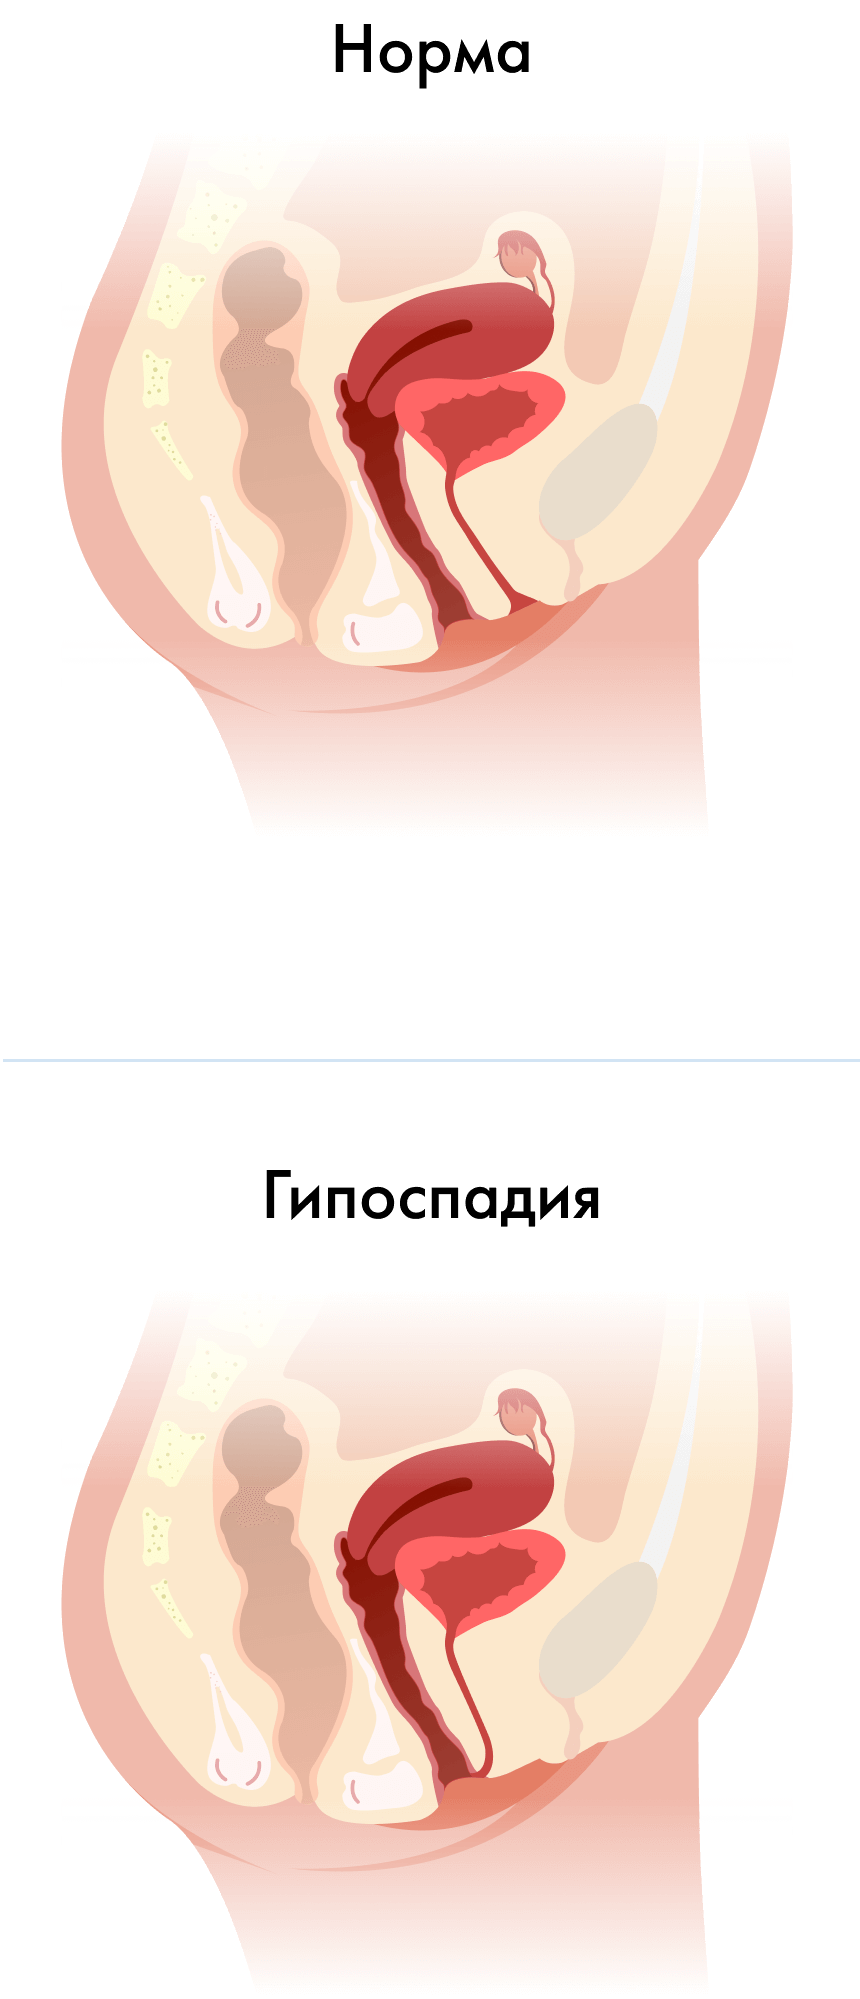

- смещение (эктопия) наружного отверстия уретры к входу во влагалище, а иногда даже на его переднюю стенку. Может сопровождаться недоразвитием и укорочением уретры;

Гипоспадия у женщин

- Атипичное расположение внешнего отверстия уретры.